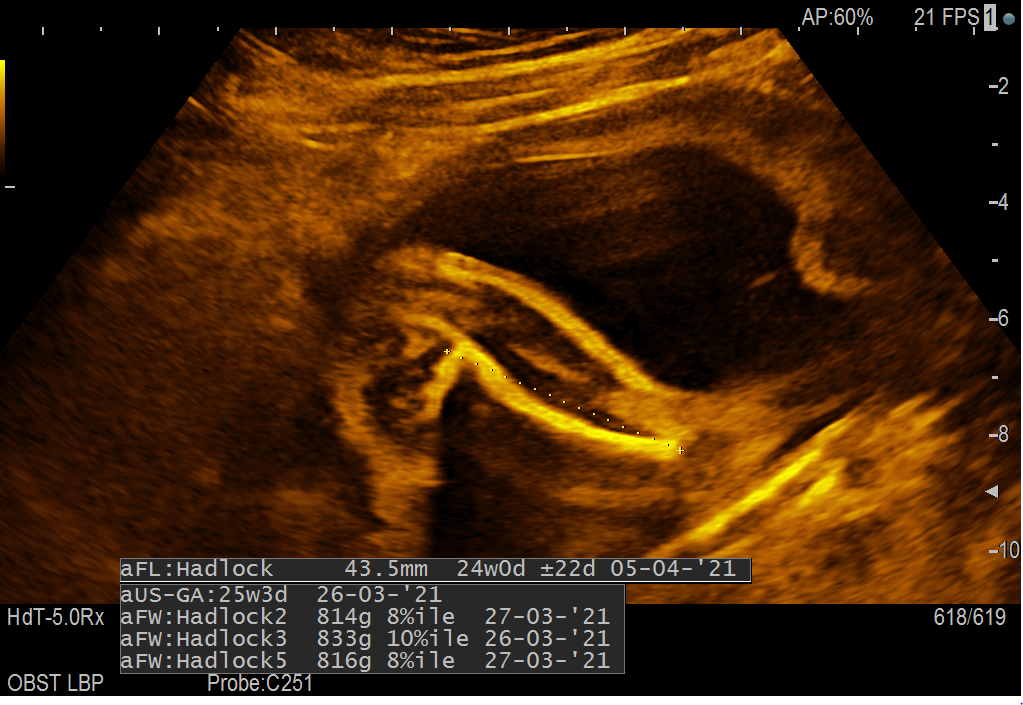

Sem v 26t4d in nosim fantka. Ginekologinja je opravila osnovno morfologijo. Plod je bil postavljen na glavo in je imel tako roke, kot noge ob glavici. Opazila ja, da je stegnenica (FL) krajša in skupaj z ostalimi meritvami naj bi komaj ujeli spodnjo normalo. Stegnenica po meritvah odstopa za 18 dni. Prilagam vam tako sliko vseh meritev, kot sliko stegnenice. Glede na to, da so do sedaj meritve UZ nakazovale na to, da razvoj ploda ustreza njegovi gestacijski starosti (oz. jo celo rahlo »prehiteva«) me zanima, ali bi me moralo sedaj to nezanemarljivo odstopanje skrbeti. Za občutek podam še osnovne meritve morfologije opravljene v 20t4d (BPD-53; HC-192; AC-151; FL-32; teža=352 g). Ponovljena morfologija v 24t naj bi bila ok (meritev ginekologinja ni zapisala).

Dodatno, se mi je doma ob gledanju slik pojavilo še sledeče vprašanje – Kaj predstavlja kost nad merjeno stegnenico (nad črtkano linijo, ki predstavlja meritev)? Desno od desnega križca meritve naj bi bila rokica, ki je bila pred obrazom, tako kot nogica. Ali je možno iz te slike razbrati, da gre za meritev spodnjega dela noge (golenice/mečnice) in ne meritev stegnenice, ki naj bi bila ena kost (rečeno nam je bilo, da rumene poudarjene linije predstavljajo kosti)?